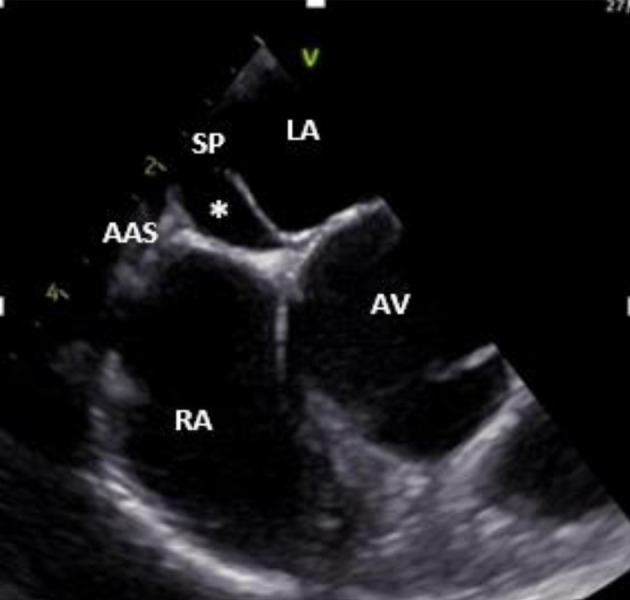

双房间隔(DIAS)现象是一种特别罕见的房间隔畸形亚型,其特点是存在双膜将心房分隔开来,形成一个独特的心房间隙。这种独特的解剖结构与矛盾性右向左分流有关,可能导致栓塞性缺血性脑卒中。在此背景下,我们报告了一例罕见病例,患者是一名 34 岁女性,突发短暂性脑缺血发作(TIA),被诊断为卵圆孔未闭(PFO)和邻近的一个小的房间隔缺损(ASD),并伴有 DIAS。经食道超声心动图和心脏磁共振成像(MRI)证实了这一诊断,并使用经导管封堵器成功治疗了该病。

The phenomenon of double interatrial septum (DIAS) represents a particularly rare subtype of atrial septal malformation, characterized by the presence of dual membranes separating the atria, resulting in a distinctive interatrial space. This unique anatomical structure has been linked to a paradoxical right-to-left shunt, potentially contributing to embolic ischemic strokes. Within this context, we report a rare case of a 34-year-old female who presented with a transient ischemic attack (TIA) and was diagnosed with patent foramen ovale (PFO) and a small adjacent atrial septal defect (ASD), along with the presence of a DIAS. The diagnosis was confirmed wit transoesophageal echocardiography and cardiac magnetic resonance imaging (MRI), and the condition was successfully treated with a transcatheter occluder device.